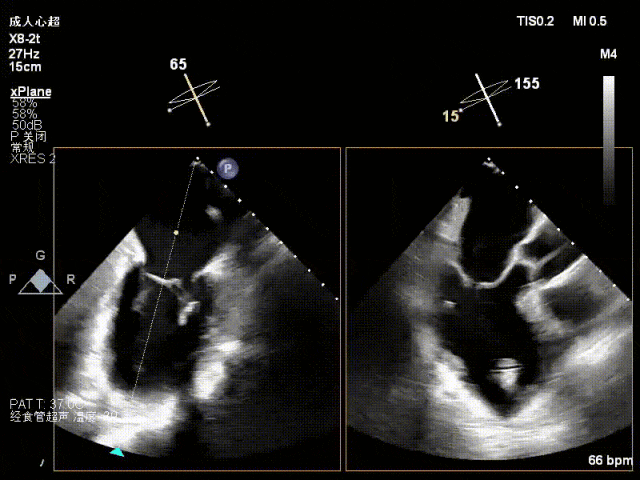

术前心超

功能性MR,P3脱垂,新分型:BAA型

反流主要集中于3区,MR中度,VC:2×4mm

A2:24mm,P2:16mm,AP:38mm,MVA约4.6cm²

术中超声要点